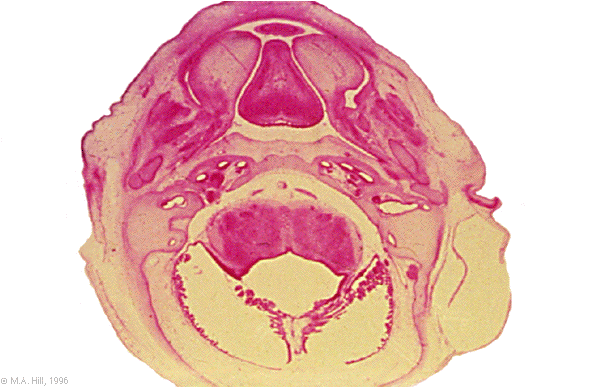

Hum B5